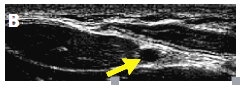

(4)纵向定位下置管:纵向定位的情况下也可进行置管(图5)。超声探头纵向确定血管位置。桡动脉成像处于屏幕中央位置后,旋转探头90°。在屏幕中央可见动脉,并确定长轴及血管最大直径处。

图5.纵向定位下的置管

超声探头纵向定位(A)桡动脉,针尖刺入桡动脉(B)

以15°~30°角进针,使针尖与血管长轴保持平行向前推进。如果屏幕上不见针头显影,其可能是在血管壁或血管外,回撤留置针,但不完全撤出,只调整角度使针尖显影可见于屏幕。再次向前推进针尖,直至其进入管腔,并见回血。保持留置针内细针位置不变,将套管继续向前推进,其后撤出留置针内细针,并将压力传感器与留置针套管连接。